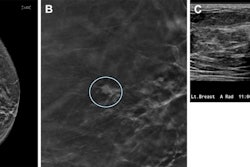

Batch reading of digital breast tomosynthesis (DBT) exams can improve the reading performance of radiologists, according to research published November 12 in Radiology.

A team led by Craig Abbey, PhD, from the University of California, Santa Barbara found that radiologists achieved improved recall rates and interpretation times without change in sensitivity in batch reading screening DBT exams.

Previous studies suggest that imaging readers experience perceptual adaptation when interpreting batched screening mammograms. This refers to the ability to adjust and adapt to changes and eliminate distractions. The researchers noted that perceptual adaptation could serve as a mechanism for better reading performance for radiologists.